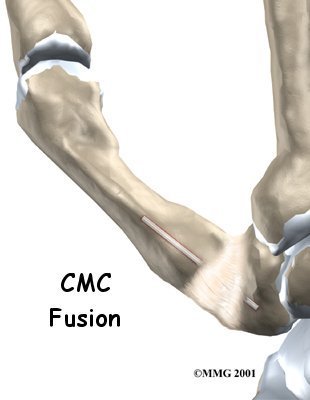

Thumb Fusion Surgery

Thumb arthritis may be surgically treated with a fusion procedure. The bones that form the thumb joint are set so they can grow together, or fuse. A fusion keeps the problem joint from moving so that pain is eliminated.